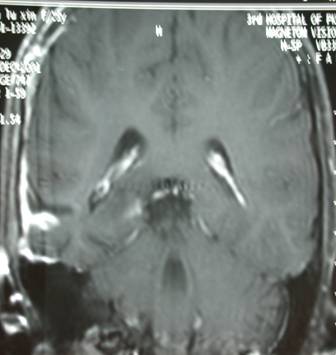

右颞深部胶质瘤

男性,40岁,主因,癫痫发作入院,查MRI示:右颞胶质瘤。

术前影像